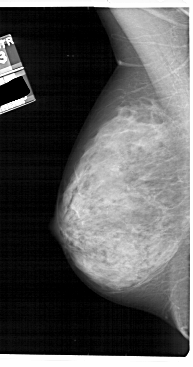

A_1912_1.LEFT_MLO

LEFT_MLO LINES 5491 PIXELS_PER_LINE 2881 BITS_PER_PIXEL 12 RESOLUTION 43.5 NON_OVERLAY